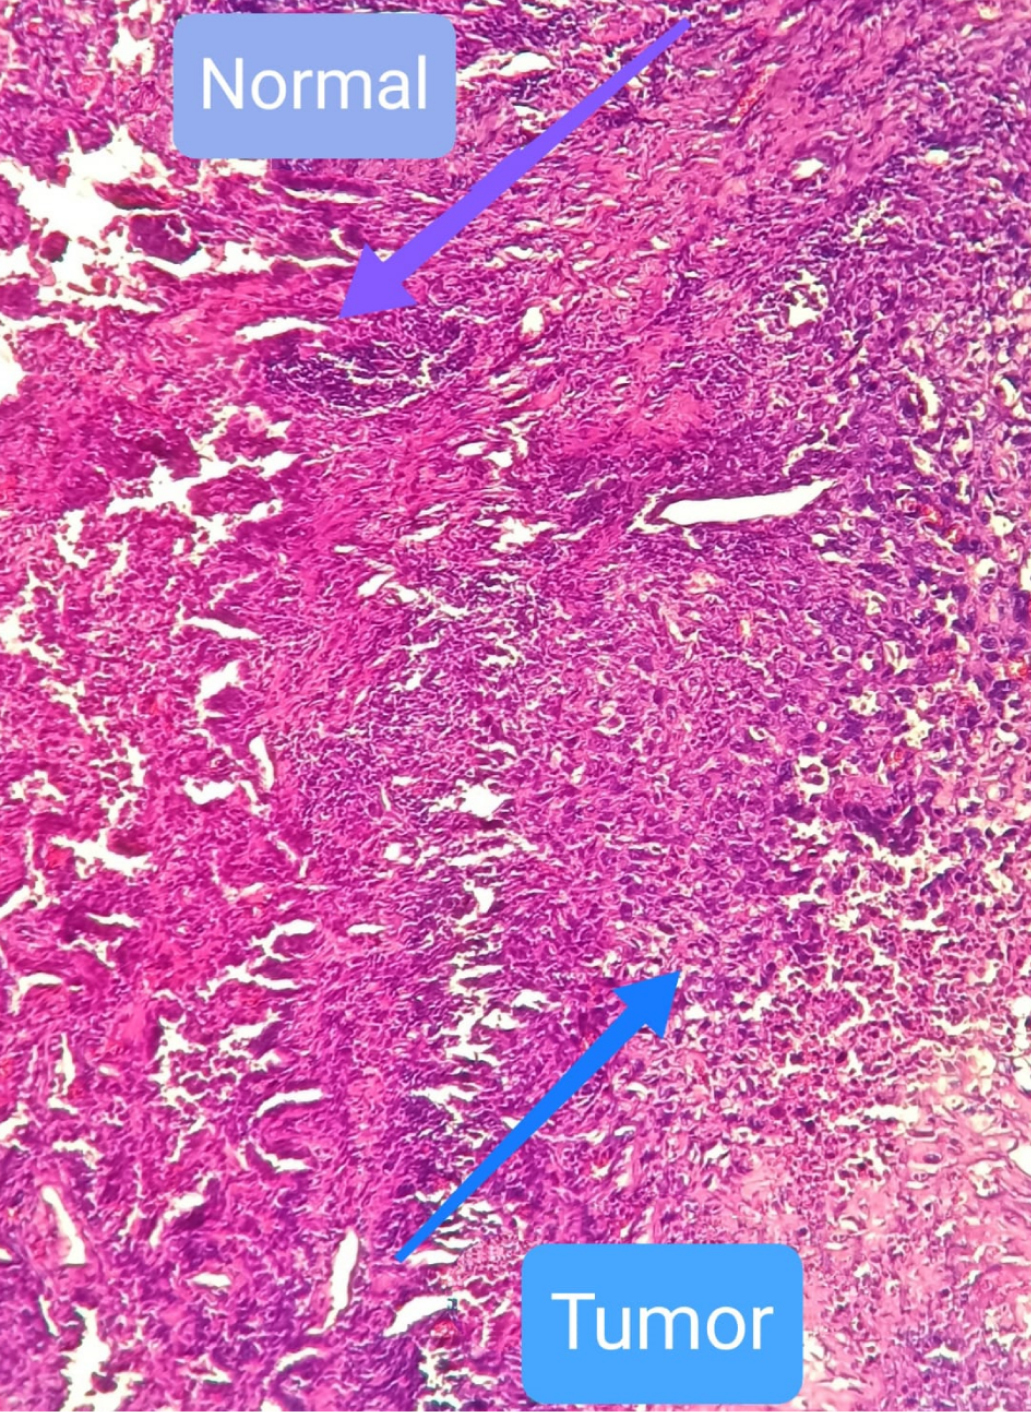

Human lung tissues were collected immediately after the surgery on lung carcinoma patients in accordance with the tenets of the Declaration of Helsinki and approved by the review board of the Azerbaijan National Center of Oncology. Informed consent was obtained from each donor. Lung carcinoma patients were selected after computed tomography. The cancer diagnosis for individuals was confirmed after biopsy and subsequent histopathological grade (aggressiveness) evaluations. Experiments were performed on five individuals. However, due to similar findings, here we report, as an example, a case of a 52-year-old male who did not receive chemo- or radiation therapy before the surgery. The results for this case were more characteristic and, therefore, analyzed thoroughly. The pathology findings on the surgical lung tissue were consistent with Stage II, pT2bN0Mx, non-small cell lung cancer. Bulk lung tissue was segregated into cancer (carcinoma) and neighboring normal (also referred to as healthy) tissues by the pathologist. Normal and cancer cells in the investigated lung tissue are indicated in Fig. 1. Experiments with spin-labeled lauric acid (C12SL) were performed with the surgical tissue of the patient with the following pathology findings: 53-years-old male, lung adenocarcinoma, Stage II, pT3N0Mx.ICD-O: 8260/3, invasive.

Fig. 1. Normal and cancer cells in lung tissue